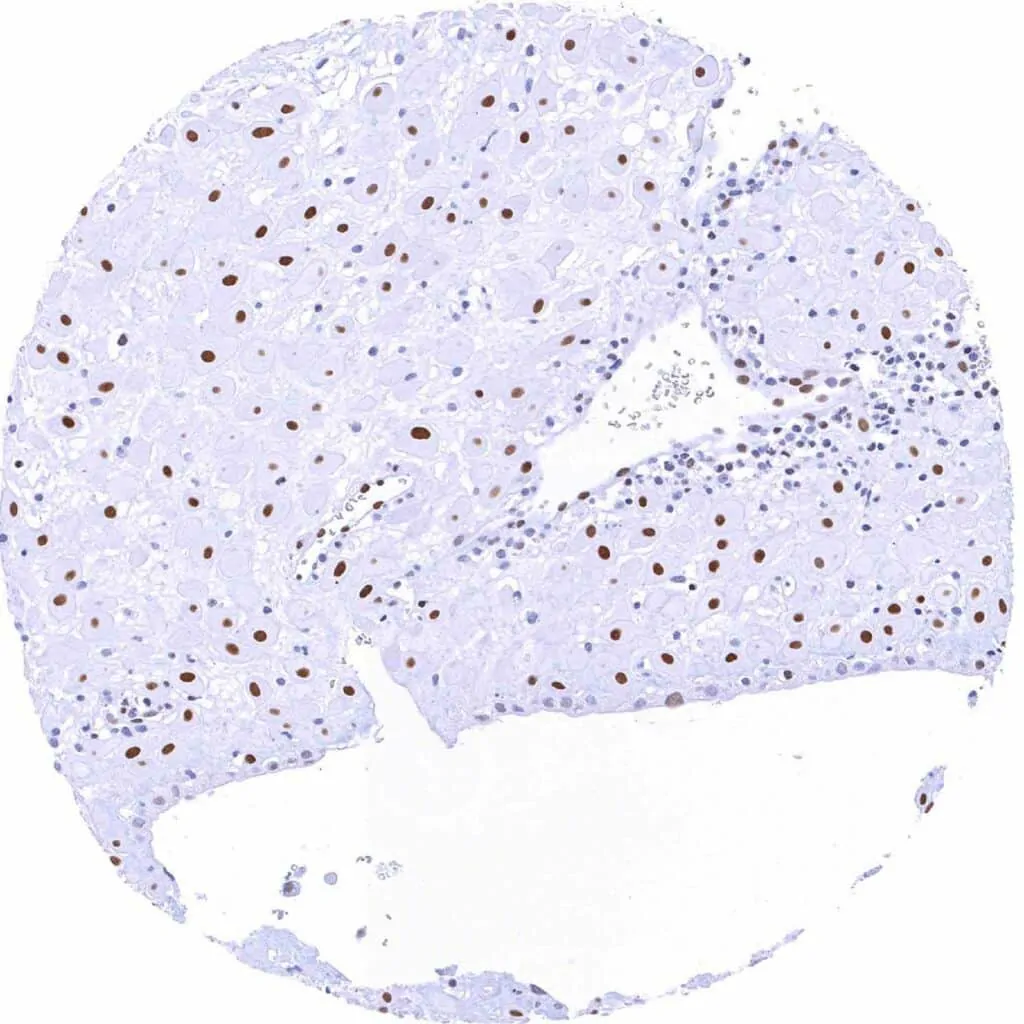

Liver – Weak to moderate TLE1 staining of bile duct cells. Faint staining of hepatocytes